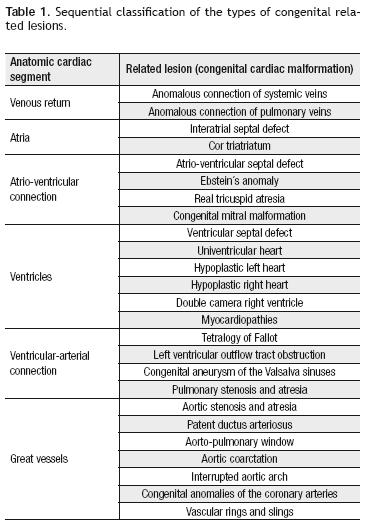

Related lesions: At this stage in the anatomic diagnosis of congenital heart disease, we will describe the related lesions, such as valvular dysfunctions, stenosis or atresia of a valve or an artery, hypoplasia, interruption or communication at any heart level. On Table 1 we propose a classification of the types of related lesions, according to the cardiac segment involved, following the anatomic sequentiality principle, in order to describe the most common heart and great arteries' congenital malformations. These lesions may appear isolated or combined as in tetralogy of Fallot.